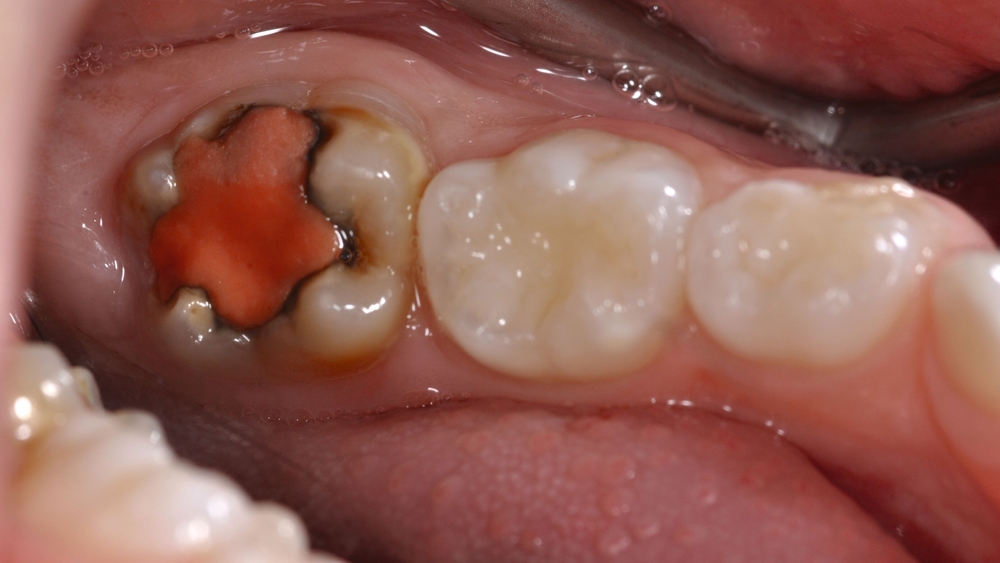

Therapie F: Extraktion

Der Therapieplan wird unverändert mit der Therapie F, der Extraktion, abgeschlossen. In schweren Fällen, wenn zum Beispiel Sechsjahrmolaren mit MIH massive posteruptive Einbrüche der Zahnhartsubstanz aufweisen, die Pulpa betroffen ist oder Zahnabszesse vorliegen, ist eine geplante Extraktion mit anschließender Einstellung der Zwölfjahrmolaren sowie der Weisheitszähne eine Behandlungsoption (Abbildung 11).

Allerdings sollte vor der geplanten Extraktion eines Sechsjahrmolaren eine radiologische und kieferorthopädische Beurteilung der Gebisssituation erfolgen [Brusevold et al., 2022], um die Anlage der bleibenden Zahnkeime zu überprüfen und mögliche Dysgnathien zu diagnostizieren [Ashley and Noar, 2019]. Zusätzlich sollte der optimale Zeitpunkt für eine geplante Extraktion gewählt werden [Lygidakis et al., 2022].

Auch wenn ein Alter von acht bis zehn Jahren als geeigneter Zeitpunkt für die Extraktion eines Sechsjahrmolaren gilt, ist der spontane Lückenschluss nicht immer gewährleistet [Ashley und Noar, 2019]. Insbesondere bei der Extraktion von Sechsjahrmolaren im Unterkiefer gilt der spontane Lückenschluss als weniger wahrscheinlich als im Oberkiefer [Brusevold et al., 2022].

In Anbetracht der Tatsache, dass bei ausbleibendem spontanen Lückenschluss nach der Zahnextraktion eine kieferorthopädische Behandlung indiziert sein kann [Jälevik und Möller, 2007], ist eine sorgfältige Aufklärung und die Berücksichtigung der Wünsche der Kinder und deren Sorgeberechtigten wichtig, um im Einzelfall die bestmögliche Therapieentscheidung zu treffen.